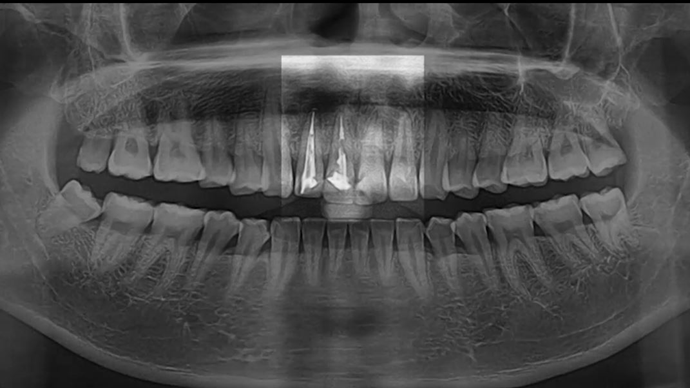

Clinical case: Extraction, immediate placement & loading using

R2GATE solution in aesthetic zone

- Courtesy of Dr. Jong-Cheol Kim, Korea-

Dr. Jong Cheol Kim, immediate loading, digital guided surgery, Digital ONE-DAY Implant, maxillary anterior, #21, guided surgery, immediate loading, AnyRidge, R2GATE, Mega ISQ, MEG Torq, R2GATE Full Surgical Kit

AnyRidge implant system, R2 Guide, R2GATE Full Surgical Kit, Mega ISQ